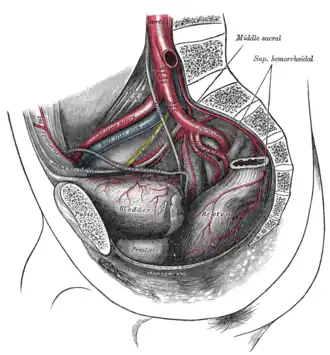

Male hypogastric artery

Male hypogastric artery -